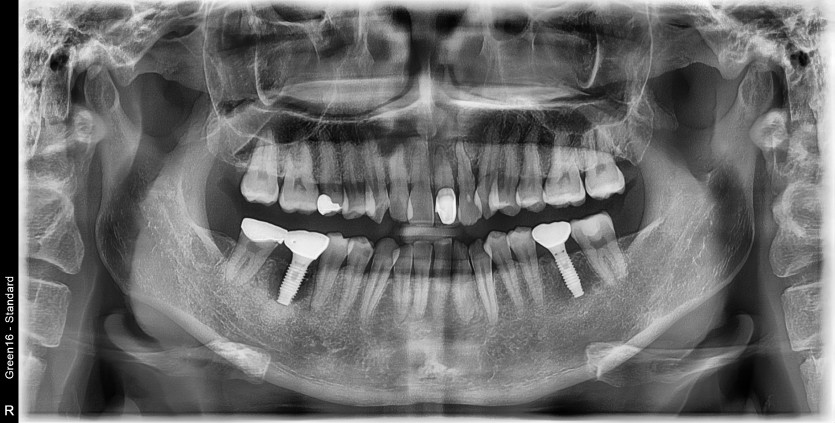

#46 타원 임플란트 제거 후

임플란트 재수술 + 치조골 이식술 시행하였습니다.